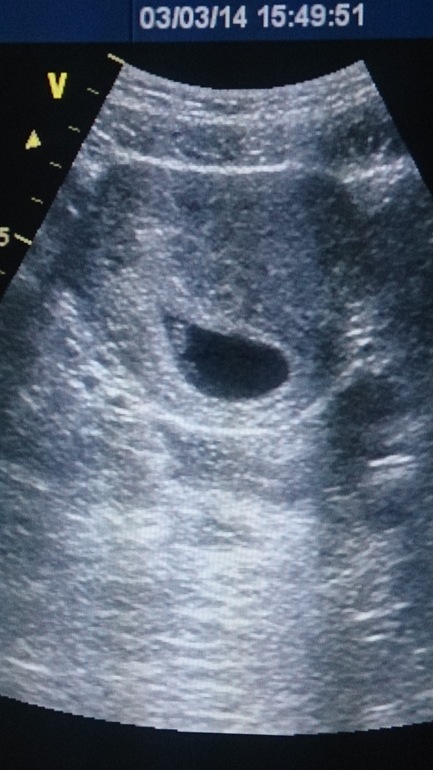

Результаты: УЗИ, КТГ, доплера, скринингаСегодня пошли с мужем на узи, муж чуть не заплакал, когда увидел как сердечко бьется))))) ну а я естественно не сдержала слезы, очень понравилась врач, все рассказывала,показывала, хотя толком еще и показывать нечего, и тем не менее))))) мы счастливы)))) фото 3 недели назад и сегодня